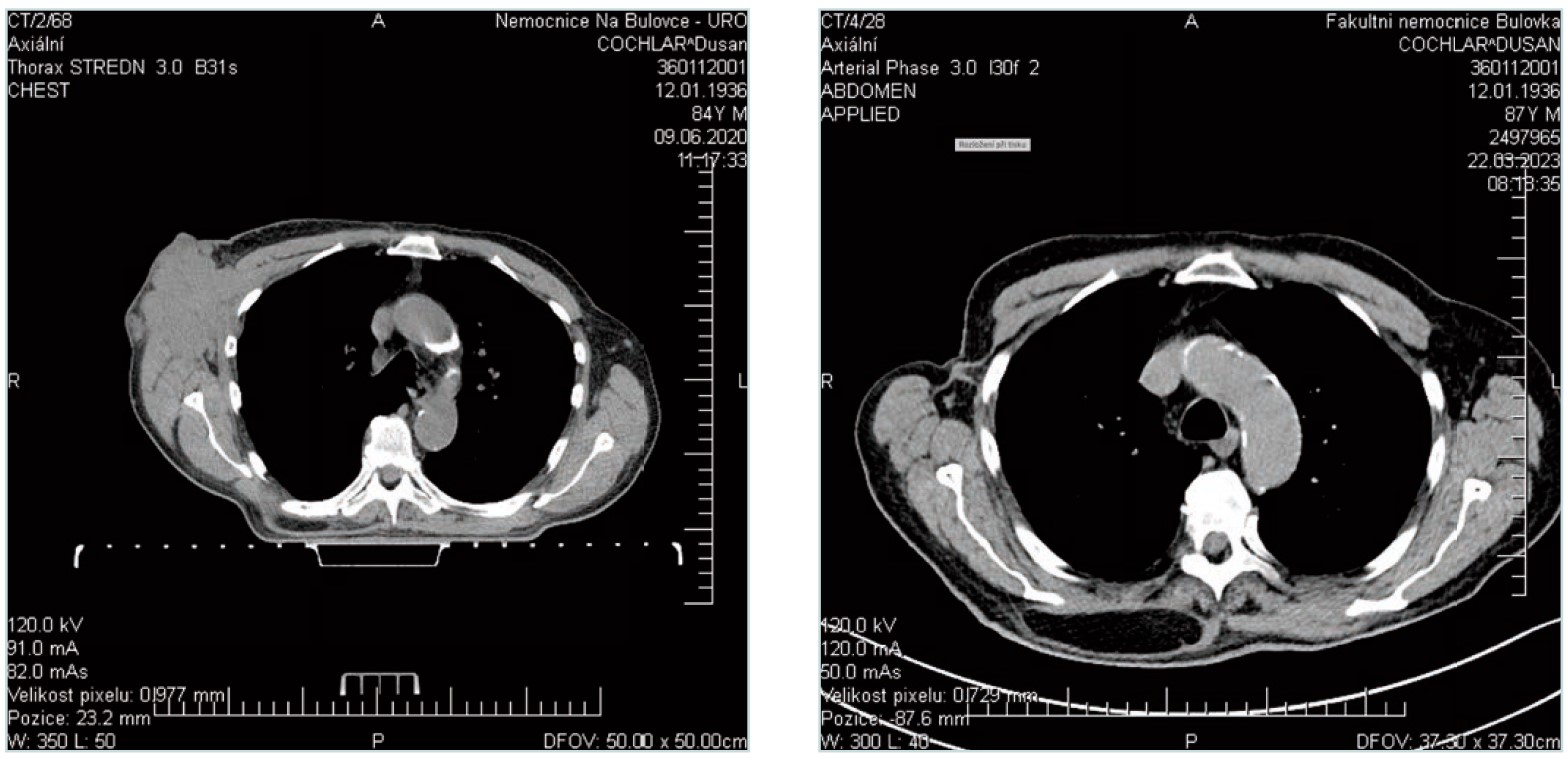

OBRAZOVÁ DOKUMENTACE:1

Snímek axilly před zahájením léčby a po jejím ukončení. Dokládající dosažení kompletní regrese.

Před zahájením léčby:

Po ukončení léčby: